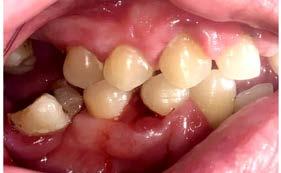

Introducción: Diversos factores locales y sistémicos, así como terapias farmacológicas tienden a tener repercusión en el estado de la cavidad oral. Una de tantas alteraciones de este tipo es la hiperplasia gingival farmacoinducida, su aparición se asocia principalmente a fármacos. Uno de ellos son los bloqueadores de canales de calcio (antihipertensivos), como el amlodipino. Descripción del caso: Paciente masculino de 45 años, acude a consulta dental, manifiesta tener dolor, sangrado e inflamación generalizada en las encías, en su historia clínica comenta ser hipertenso desde hace 8 años por lo que se encuentra bajo tratamiento farmacológico con bloqueadores de canales de calcio. Gracias a los hallazgos clínicos y radiográficos se le diagnostica periodontitis generalizada, estado IV, grado

C, por lo que se le ofrece un plan de tratamiento de rehabilitación oral. Conclusiones: Se ha comprobado que el amlodipino es el fármaco causante más común con la capacidad de inducir el desarrollo de una hiperplasia gingival. A pesar de no existir evidencia de que la destrucción de los tejidos de soporte sea una secuela de la hiperplasia gingival, la condición periodontal con ausencia de tratamiento puede empeorar la ya establecida y la infección se puede extender a otros órganos o sistemas de órganos, lo que es de vital importancia tratar de evitar en pacientes sistémicamente comprometidos y farmacodependientes.

Descripción del caso

Paciente masculino de 45 años de edad, acude a consulta dental a la Clínica Integral de Ciencias de la Salud de la Universidad Autónoma de Baja California en la ciudad de Tijuana, manifiesta tener dolor, sangrado e inflamación generalizada en las encías, en su historia clínica comenta ser hipertenso desde

hace 8 años por lo que toma 30 mg de nifedipino cada 12 horas, amlodipino 5 mg cada 24 horas, telmisartan 40 mg cada 12 horas y metropolol 100 mg cada 12 horas, además comenta padecer diabetes mellitus tipo II desde hace 7 años por lo que también toma 50 mg de metformina cada 12 horas y dapagliflozina 10 mg cada 24 horas. Clínicamente se observó una encía roja y sangrante, profundos sondeos, una notable hiperplasia gingival, depósitos de cálculo y movilidad dental grado III en todos los órganos dentarios a excepción del segundo premolar superior derecho al canino superior izquierdo, quienes presentaban una movilidad grado II. Radiográficamente se encontró una pérdida de inserción radiográfica avanzada generalizada

en la arcada inferior, y grupos molares de ambos cuadrantes superiores (Figura 1), los únicos órganos dentarios con posibilidad de preservación en boca a través de terapia periodontal se encontraron en el sector anterior de la arcada superior anteriormente mencionados con movilidad grado II

(Figura 2). Por lo que se diagnostica con periodontitis generalizada, estado IV, grado C (Figura 3).